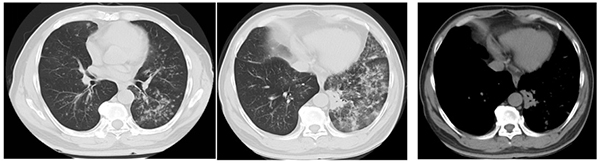

治疗前(2018年6月)

赵先生并无吸烟史,却有肺癌家族史(父亲患肺癌),这提示了遗传背景在肺癌发生中的潜在影响。2018年6月,他在外院的胸部CT提示双肺弥漫结节影,左肺斑片状实变影伴磨玻璃影,初步诊断考虑为“肺结核可能”。转至北京胸科医院结核科后,痰涂片中发现腺癌细胞,结核病相关检查均为阴性,2018年8月最终明确诊断为肺腺癌IV期。基因检测结果显示EGFR基因突变(为比较复杂的复合突变19-Del/T790M/20-Ins),这为后续靶向治疗提供了关键依据,也为患者带来了极大的希望。

赵先生,58岁,一个普通的公园管理员,每日与绿树清风为伴。2016年起,他开始出现咳嗽、咳痰症状,起初并未在意。2017年11月,他的咳嗽症状加重,并伴发胸闷气短,但他仍未就诊,直至2018年6月,胸闷气短明显加重,他才去医院检查胸部CT,发现双肺弥漫分布的结节影,一度被怀疑为“肺结核”,然而,真相在北京胸科医院结核科得以揭晓——痰涂片中查见腺癌细胞,最终确诊为左肺下叶腺癌,伴随双肺转移、纵隔淋巴结转移,临床分期为IV期(最晚期肺癌)。